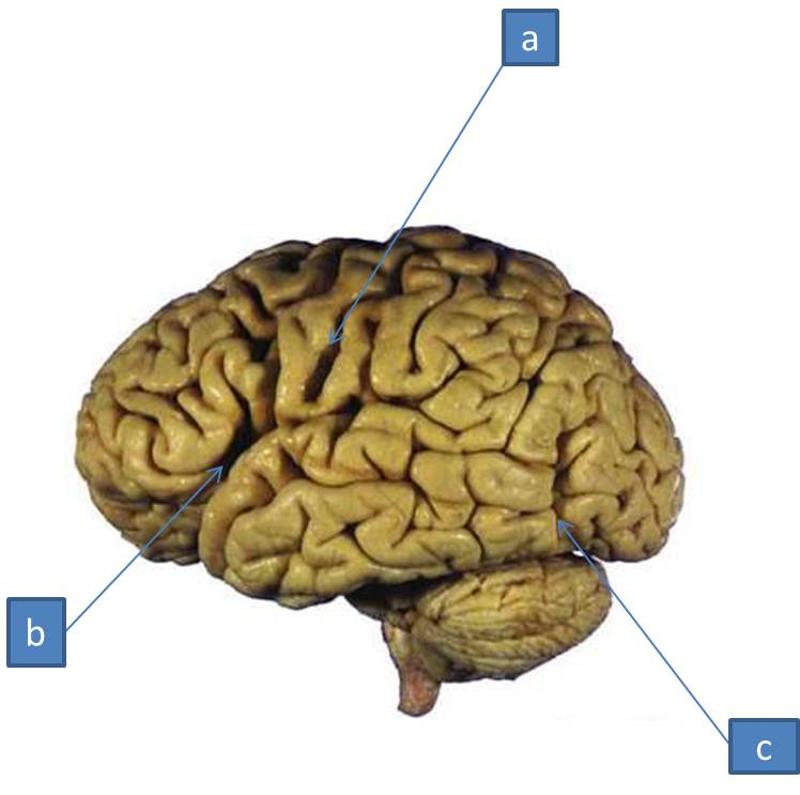

Супрамаргинальная извилина: Функции и Исследования